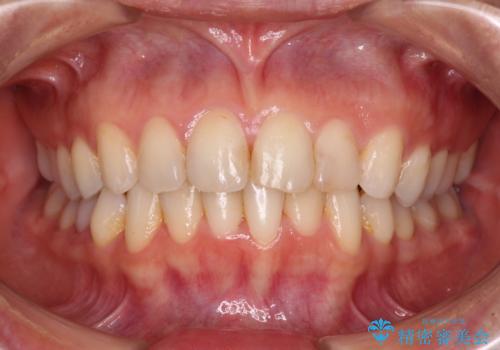

それでも、しっかりとマウスピースを装着してくださったので、大きなトラブルもなく治療を終えることができました。

- 前歯のクロスバイトを気にして来院され患者様です。